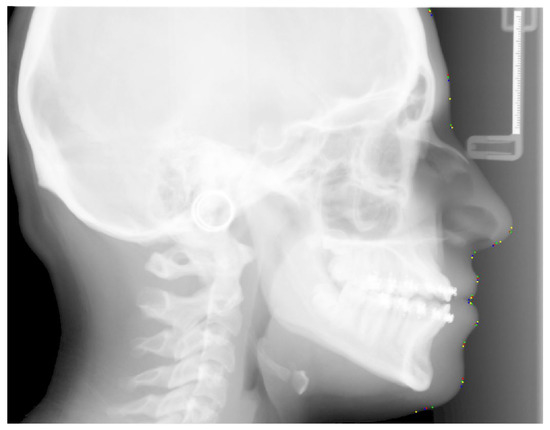

The borders of the soft tissue in the initial X-ray images are not clearly visible due to poor contrast, and hence we need to apply some preprocessing steps, i.e., to use the gamma correction method to sharpen and increase the contrast of the borders of the soft tissue.

In Figure 1, we show a sample X-ray image before and after applying the gamma correction. It is clear that after applying the gamma correction, the soft tissue borders are now visible for further usage. In our tool, we first preprocess all X-ray images using the gamma correction before performing actual annotations.

Figure 1. Effect of gamma correction of a sample X-ray image.